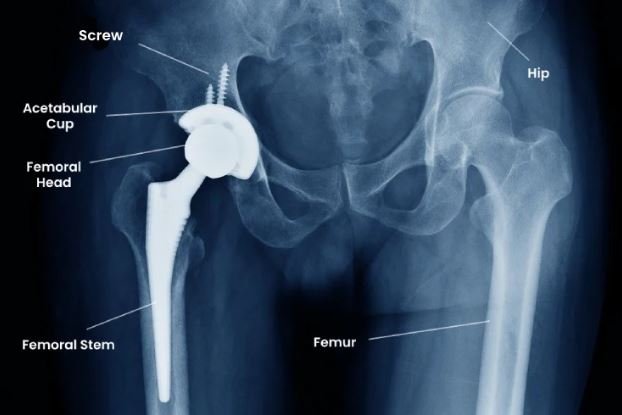

Understanding Total Hip Replacement

Total hip replacement, or total hip arthroplasty, is a procedure in which the damaged ball-and-socket joint is replaced with artificial components. According to Dr. Ponnanna, the most common reasons patients seek hip replacement in bangalore include:

Modern implants are designed to mimic natural joint movement and are made of durable materials such as ceramic, polyethylene, or metal alloys.